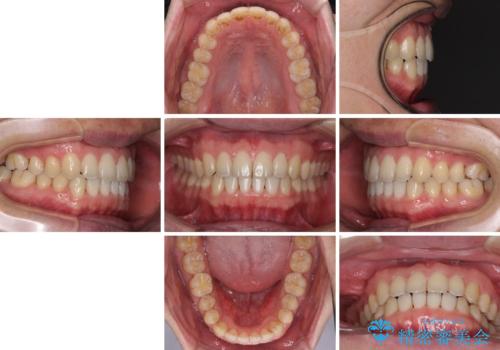

- 上の前歯の隙間を気にして来院された患者様です。

インビザラインにより、上下の歯列を側方に拡大しつつ、前歯の隙間を閉じていくこととしました。

1日22時間の装着時間をしっかりと守ってくださったので、隙間がきれいに閉じ、口元の突出感も改善することができました。